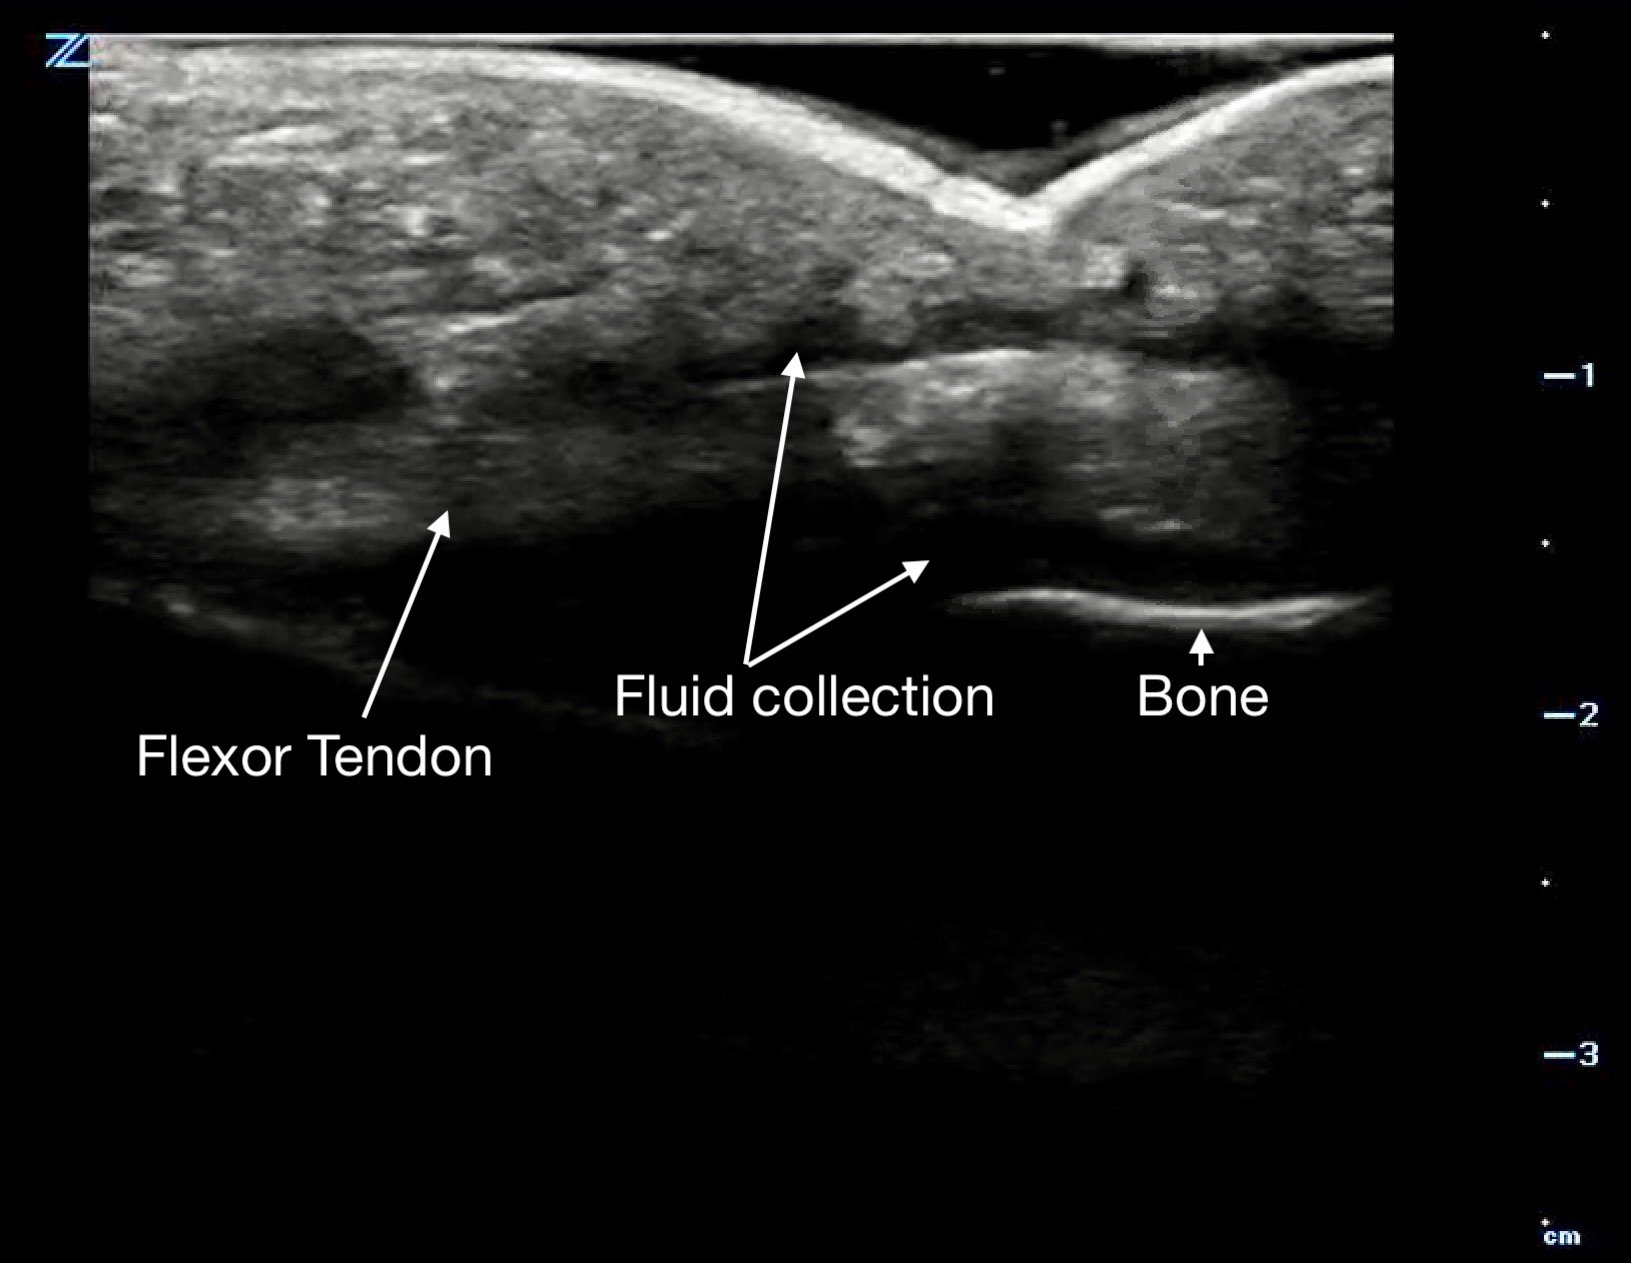

Figure 14a.

Flexor tenosynovitis demonstrated by the halo of fluid in the sheath surrounding the tendon

Figure 14b.

a long axis view with fluid above and below the flexor tendon.